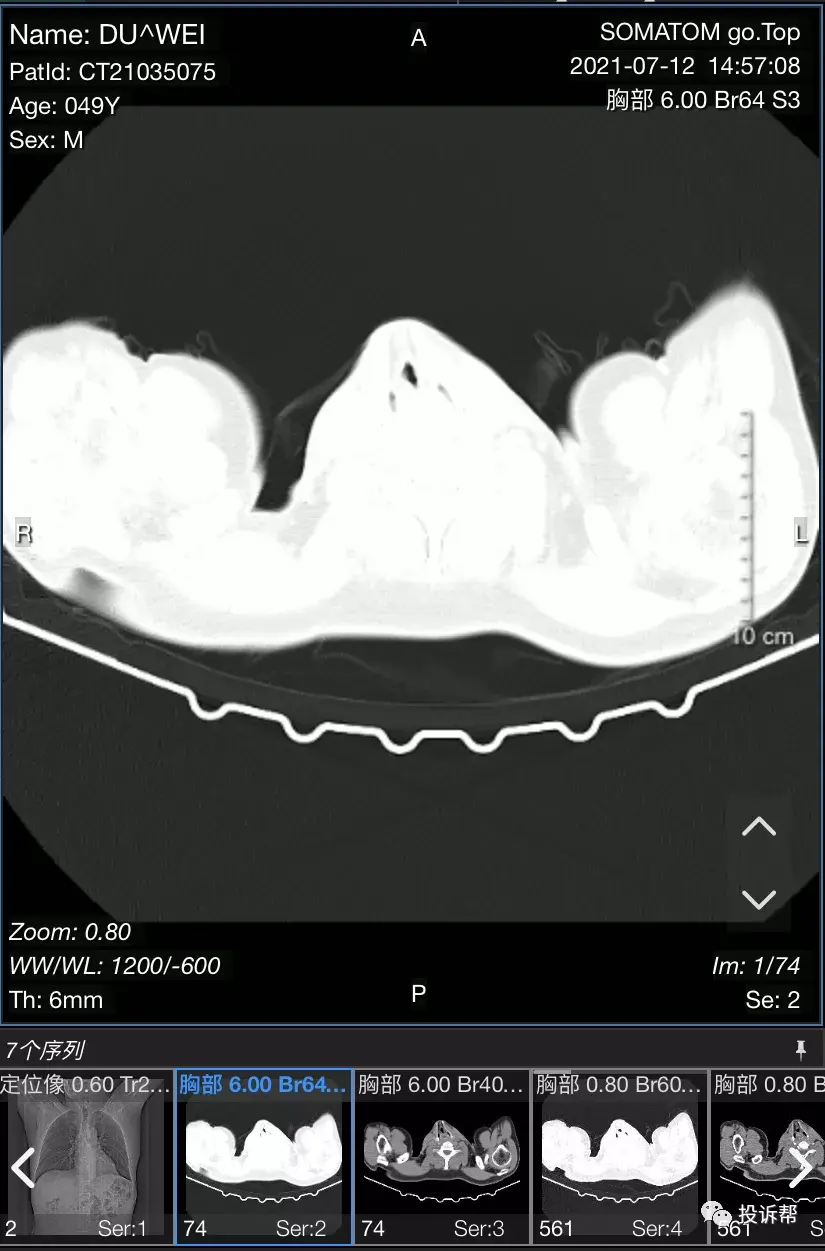

对此,杜先生回答道:“首先没有发生过这种病症,CT检查不出来,又没有长肿瘤,没有破裂,也没有出血……膈肌脚在膈肌下面,根本看不到膈肌脚。”

杜先生通过投诉帮的豹料云系统,上传了自己的CT三维重建影像。

“三维重建的(影像)可以看到已经把脊柱拉直了,脊柱应该是S形弯曲,因为膈肌脚拉长了之后把脊柱顶着。”